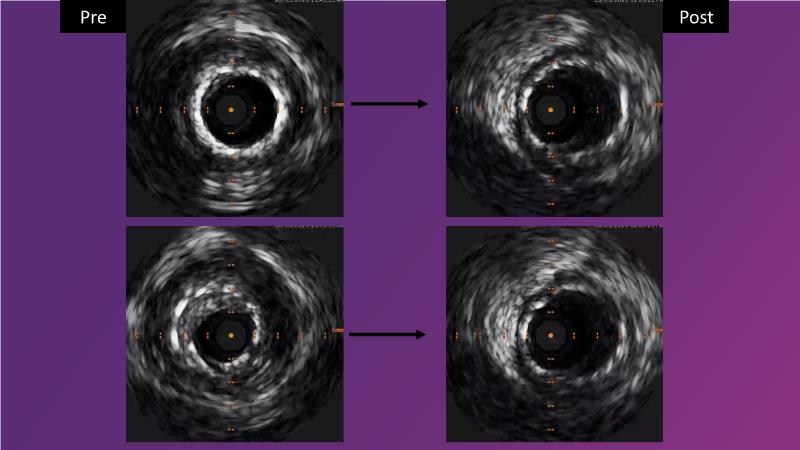

Watch this session to gain case-based insights on using DCBs in complex settings. Learn valuable tips and tricks for optimal DCB application, including the best timing and situations for their use. Discover how to effectively implement a hybrid strategy that combines DES and DCB when needed.

- To get a case based experience on how to use a DCB in complex settings

- To learn about tips and tricks on how and when to use a DCB: the ideal time and situation of DCB application in various complexities